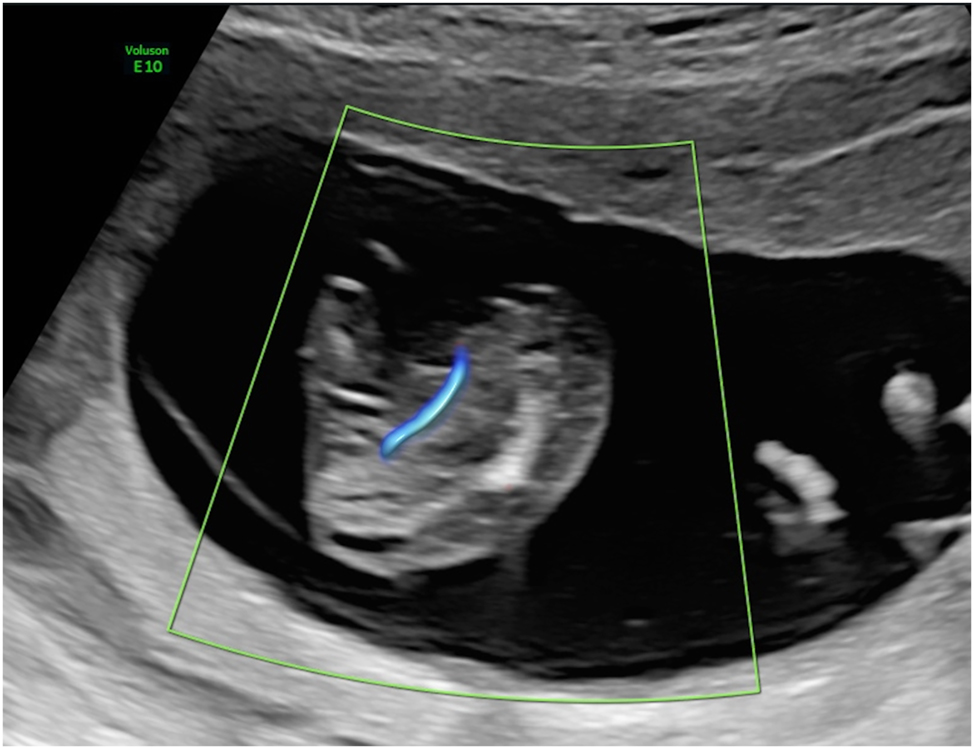

The procedure of intrafetal laser (Figure 8) involves inserting an 18-gauge needle through the maternal abdominal wall into the amniotic cavity under ultrasound guidance, after local anaesthetic has been administered. The needle is positioned directly into the parasitic co-twin at the level of umbilical cord insertion in the pelvic region. A laser fiber is then passed through the needle to coagulate the abnormal blood supply. The thin laser fiber allows precise control of the ablation zone, which is particularly advantageous at earlier gestational ages. The laser energy ablates the blood supply to the acardiac twin, with successful occlusion subsequently confirmed by color Doppler ultrasound [8], 9], 59].

Figure 8:

Intrafetal laser therapy performed in the first trimester (A) procedural setup. (B) Ultrasound-guided insertion of an 18-gauge needle into the parasitic twin at the level of the pelvic region, targeting its vascularization. (C) Laser fiber insertion through the needle for coagulation of the vessel, resulting in complete occlusion.